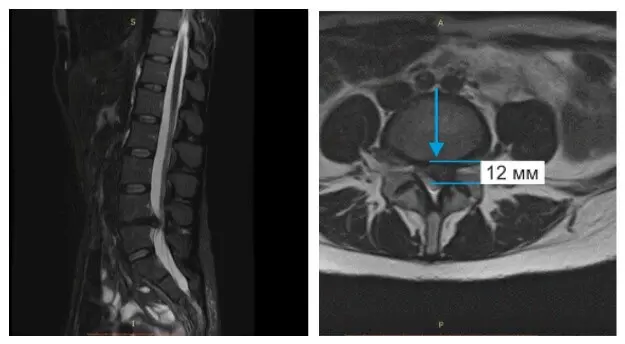

Бывают случаи, когда вправление грыжи можно провести за несколько сеансов. Иногда даже за один. Это возможно при протрузии диска и грыже небольшого размера. Если же грыжа большая и сопровождается болью в ноге, то для излечения понадобится курс лечения. Как это было с одной из наших многочисленных пациентов Ириной, результаты чего видны на МРТ, что ниже.